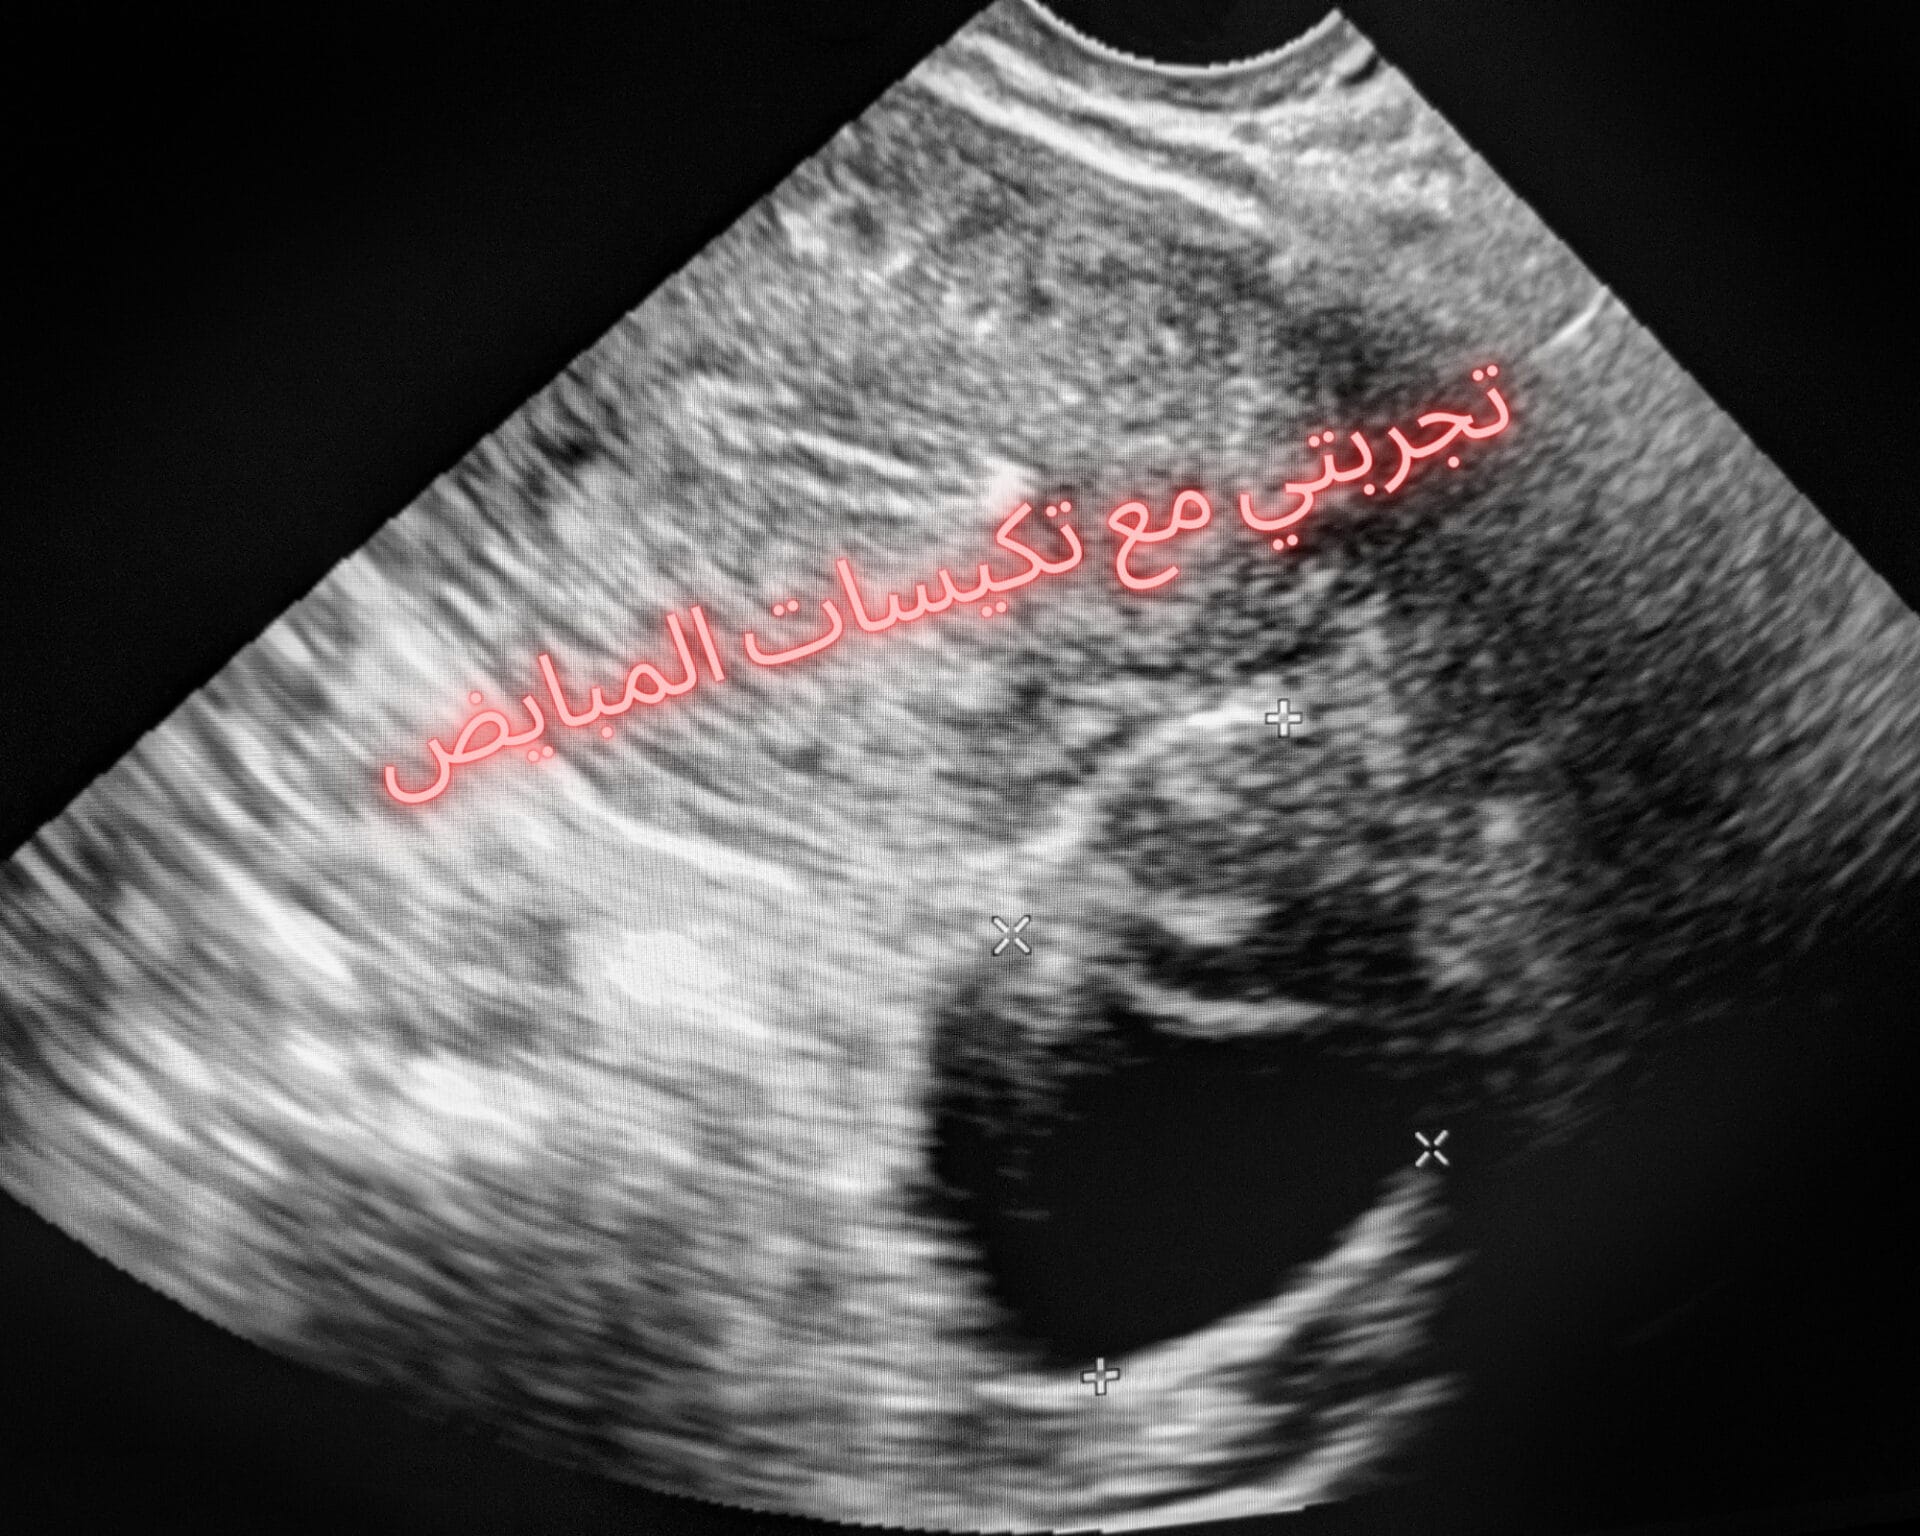

تجربتي مع تكيسات المبايض

تقول إحدى السيدات بدأت معاناتي مع تكيسات المبايض عند عدم انتظام الدورة الشعيرة وتأخر الإنحاب لفترة كويلة، مما جعلني اتوجه مباشرة للطبيب لأجراء التحاليل والفحوصات الطبية، وعند إجرائي لكشف السونار اكتشفت وجود بعض التكيسات المتصلة ببعضها البعض والتي تعيق حركة الحيوانات المنوية داخل الرحم منا تسبب لي عجو في إتمام عملية الخمل.

اقرأ أيضًا: تكيسات المبايض اشعة بالسونار على المبايض اسفه بزعجك بس هذي صورة الاشعه اللي عملتها الدكتوره